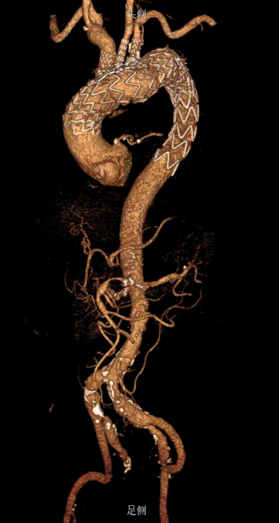

韩某,男,53岁,“查体发现主动脉弓部溃疡15天”入院,主动脉CTA提示:主动脉溃疡(弓部);2. 主动脉壁内血肿。患者高血压病史8年,最高210/130mmHg,无规律服药。

术前 CTA

术前造影

术前

术后

手术用时115分钟